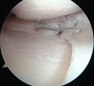

半月板は膝の内側と外側の両方に存在してクッションの役目を果たしており、外傷やスポーツなどによるオーバーユースにより損傷することがあります。また加齢による変性でも損傷します。手術では関節鏡を膝関節内に挿入して半月板の様子を確認してどのような手術を行うかを判断します。当院ではなるべく半月板を温存することを心掛けており、半月板縫合を行うことが多いですが、修復が難しい部位では部分切除が余儀なくされることもあります。

半月板を修復している鏡視所見